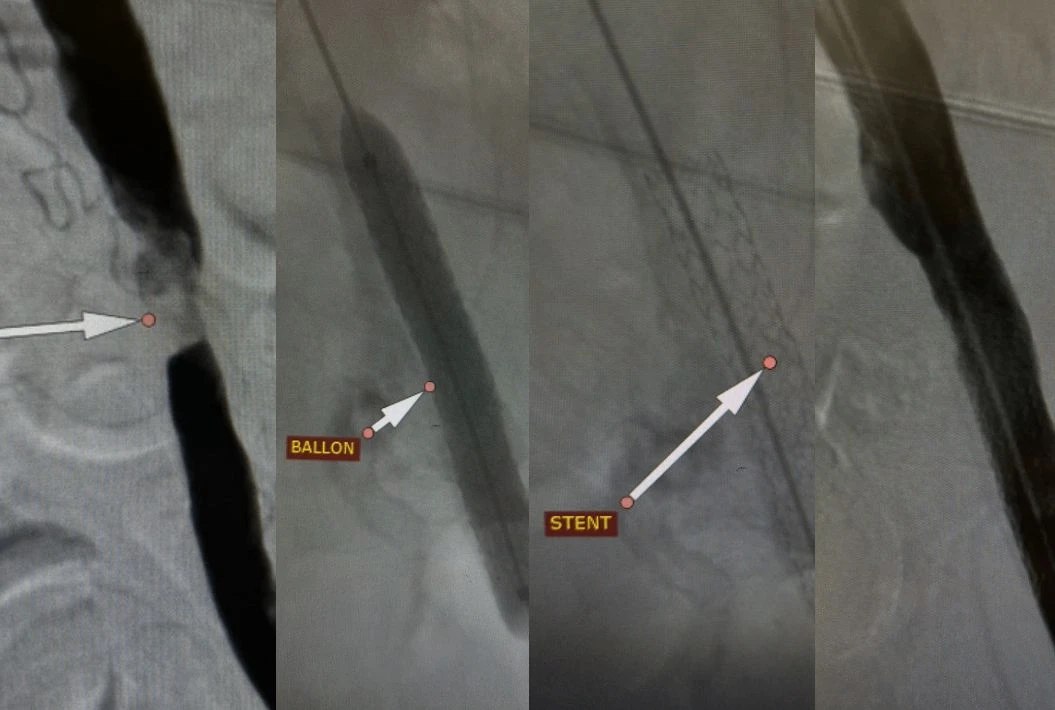

Хирурги Волгоградской больницы скорой помощи 25 провели уникальную операцию и спасли 55 летнему пациенту ногу от ампутации Мужчина испытывал сильные боли не мог ходить У него обнаружили значительное сужение артерий ноги ишемия покоя Заболевание развивается быстро образуя язвы и приводя к гангрене Через небольшой прокол в бедре ему провели так называемую рентгенэндоваскулярную процедуру когда в артерию вводят специальные каркасы стенты которые расширяют сосуды давая возможность нормализовать кровообращение А уже спустя сутки бывший больной отправился домой снабжённый рекомендациями для дальнейшего восстановления здоровья

Волгоградские хирурги спасли ногу пациента от ампутации 53 летний мужчина был госпитализирован с невозможностью наступать на больную конечность сильными болями нарушающими сон холодностью и бледностью кожи ноги Врачи выявили значительное сужение артерий ноги что опасно быстрым развитием необратимых изменений тканей вплоть до образования язв некрозов и гангрены Через небольшой прокол в бедренной артерии врачи больницы 25 выполнили стентирование подвздошной артерии для поддержания просвета сосуда Спустя сутки пациент смог самостоятельно передвигаться и покинул стационар сообщает облздрав Подписаться Перейти на сайт MAX